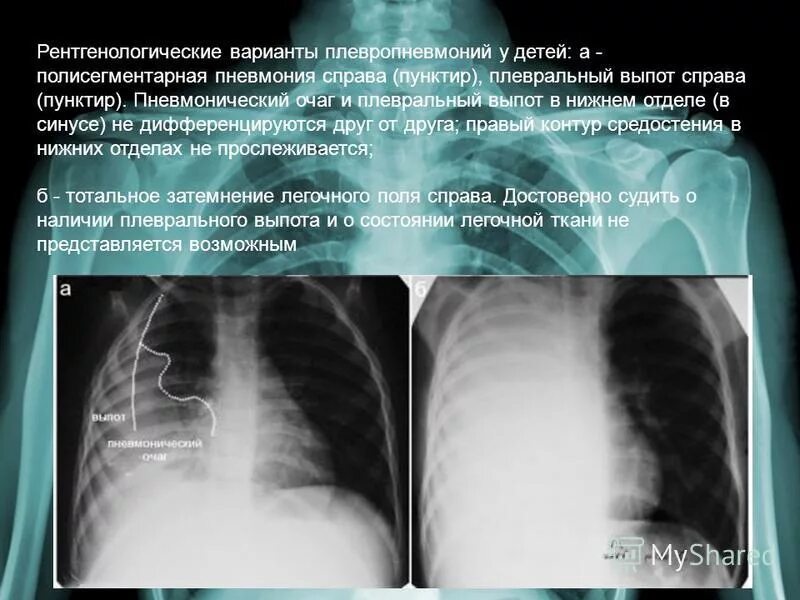

Двусторонняя сегментарная